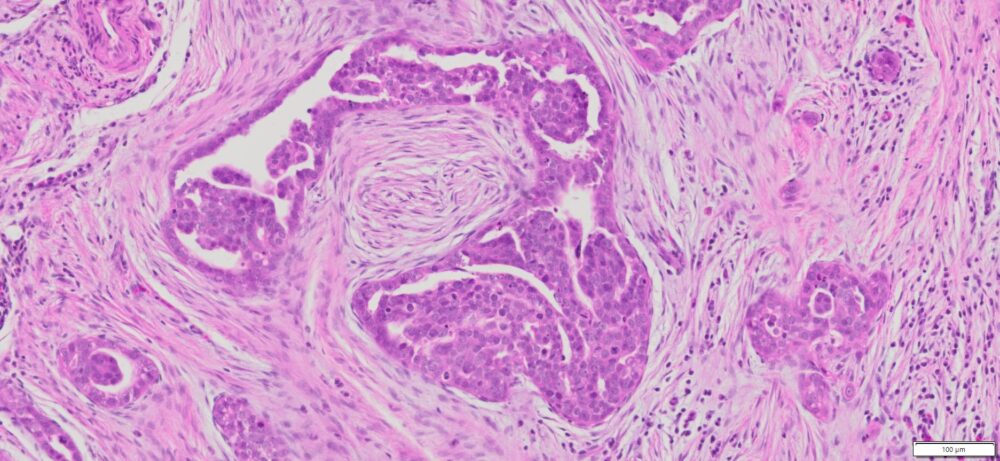

Description

| Tissue | Pathology Diagnosis | Gender/ Age (year) | %Tumor Area | Tumor Grade | TMN/Stage | IHC data |

| Omentum | Human omental high grade serous Carcinoma | Female/67 | 40% | III | NA | MOC-31(+),BER-EP4(+),P53(+), P16(+) |